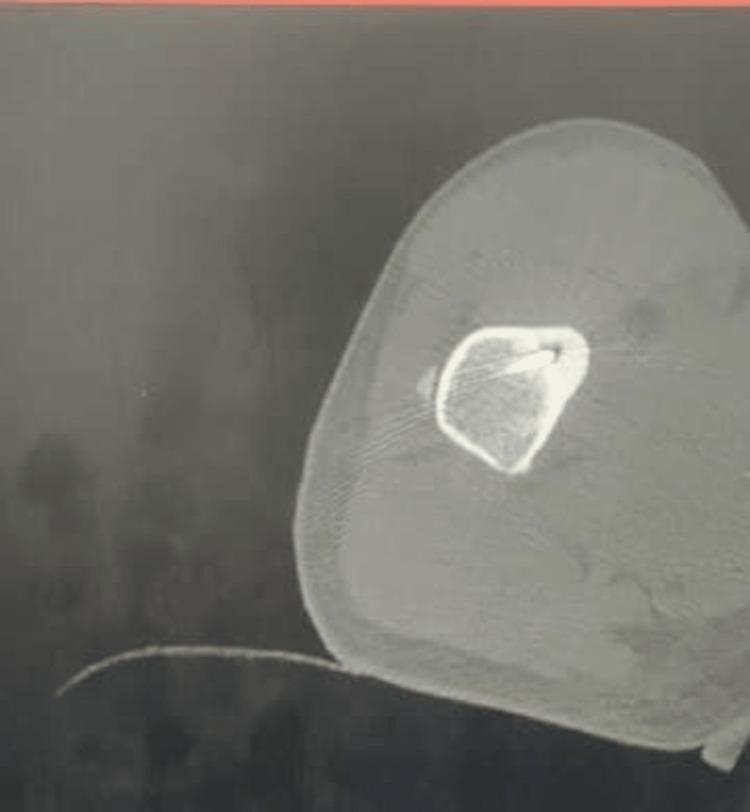

经皮CT引导下射频消融治疗骨样骨瘤的疗效

Outcomes of Osteoid Osteoma Treated by Percutaneous CT-Guided Radiofrequency Ablation.

Introduction Osteoid osteomas are the most frequent true benign bone tumor in the adolescent age group and the third most prevalent benign bone tumor overall. This study was designed to assess the effectiveness of the procedure and correlate it with the analgesia offered because of the significant burden of this illness and new literature supporting the successful outcomes of image-guided percutaneous radiofrequency ablation (RFA) in osteoid osteoma. Methodology  This hospital-based interventional trial was carried out in a tertiary care referral center. Forty-two patients with osteoid osteoma, ranging in age from 9 to 30, were included in the study. The patients received RFA guided by computed tomography (CT), and they were postoperatively monitored at one, two, and four weeks and three, six months, and 12 months. A numerical pain scale (NPS) was used to evaluate the patient's pain both before and after the procedure. The preoperative and postoperative results were contrasted. Results A total of 42 participants were enrolled in the study. Eight (19.05%) women and 34 (80.95%) men made up the group. Complete pain alleviation (NPS=0) was attained in 42.8% and 96.4% of the study group in the first and second weeks post-procedure. Almost all patients began protected weight-bearing at one week, according to their level of pain tolerance. Osteoid osteoma of the talus was a remnant lesion in one patient that required further treatment after two weeks. During the duration of the follow-up, no problems were recorded. Conclusion Percutaneous CT-guided RFA of osteoid osteoma is a safe, minimally invasive procedure and greatly reduces the duration of hospitalization. It has excellent functional outcomes and no known complications.

摘要

引言

骨样骨瘤是青少年年龄组中最常见的真正良性骨肿瘤,也是总体上第三常见的良性骨肿瘤。由于这种疾病的负担较重,且有新的文献支持影像引导下经皮射频消融术(RFA)治疗骨样骨瘤的成功结果,本研究旨在评估该手术的有效性,并将其与所提供的镇痛效果相关联。

方法

本基于医院的干预性试验在一家三级医疗转诊中心进行。研究纳入了42例年龄在9至30岁之间的骨样骨瘤患者。患者接受计算机断层扫描(CT)引导下的RFA治疗,并在术后1周、2周、4周以及3个月、6个月和12个月进行监测。使用数字疼痛量表(NPS)评估患者手术前后的疼痛情况。对比术前和术后的结果。

结果

共有42名参与者纳入研究。该组包括8名(19.05%)女性和34名(80.95%)男性。在术后第一周和第二周,研究组分别有42.8%和96.4%的患者实现了完全疼痛缓解(NPS = 0)。几乎所有患者根据其疼痛耐受程度在术后1周开始进行保护性负重。1例距骨骨样骨瘤患者在术后2周仍有残留病灶,需要进一步治疗。在随访期间,未记录到任何问题。

结论

CT引导下经皮RFA治疗骨样骨瘤是一种安全、微创的手术,可大大缩短住院时间。它具有出色的功能结局且无已知并发症。